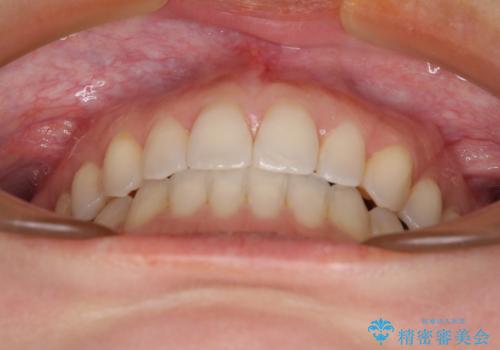

【モニター】狭い上顎歯列とオープンバイト 急速拡大装置を用いた矯正治療

- 前歯の開咬を気にして来院された患者様です。

上顎歯列が狭窄していたため、急速拡大装置により上顎骨を側方に拡大し、その後インビザラインにて矯正治療を行うこととしました。

舌の突出癖が開咬の原因であったので、改善のための舌トレーニングを行っていただきました。

舌トレーニングは後戻りにも大きく影響するため、とても重要なトレーニングです。